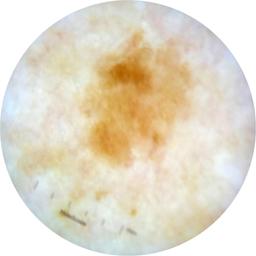

ISIC_9472333

Information

Dimensions

2057 x 2057

acquisition_day 230

age_approx 65

anatom_site_1 Trunk

anatom_site_2 Anterior trunk

anatom_site_general anterior torso

diagnosis_1 Benign

diagnosis_confirm_type single image expert consensus

image_type dermoscopic